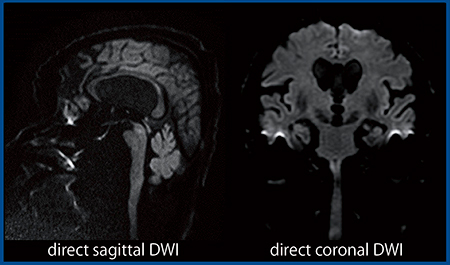

ZGOの最大の特徴は,世界最高スペックの最大傾斜磁場強度(Gmax)100mT/mである。Gmax100には高電流が必要で,通常はそれに伴い,発熱や振動,渦電流が上昇してしまうことが課題となり実現が難しかった。しかし,ZGOでは,Gradient Coilを直接冷却するDirect Coolingや,より強固なRigid Core Moldingといった新パターン設計のUltra Gradient Coilの採用により,従来の3T装置と比べて渦電流を60%,発熱量を55%,f0シフトを60%,振動を75%低減することに成功している。基本性能が大幅に向上したことで,DWIをコロナルやサジタルでダイレクトに撮像しても,驚くほど歪みの少ない良好な画像が得られる(図1)。

これらの効果でgradient dutyも大幅に向上しており,同一TRにおける撮像効率が最大50%向上している。gradient dutyが高いことは研究を行う上で非常に重要で,DWIにおけるさまざまな検討が可能となった。

図1 ZGOで得られる歪みの少ないDWI